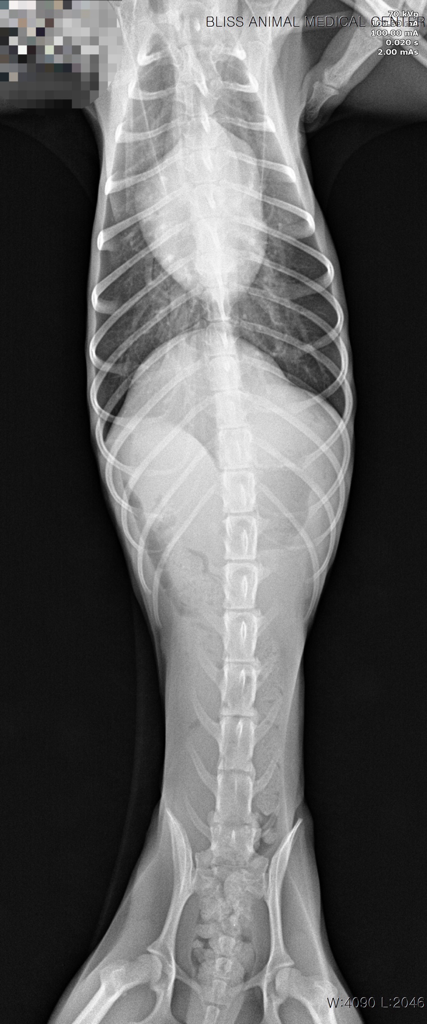

7월 16일에 강아지가 무기력하더니, 17일 새벽에 1번, 병원에서 2번, 내원 후 집에서 1번 총 4번 발작했습니다. 검사해 보니 췌장염도 있고, 심장병(단계 설명은 못 들음), 간 문제 등등 그 외에도 문제가 많이 보여서 수의사 님도 정확히 뭐 때문에 발작을 했는지 확답을 내리지 못 하셨습니다.

이 나이에 이렇게 아픈 것도, 체격/먹는 거에 비해 살이 안 오르는 것도 선천적 요인일 가능성이 높다고 하셨습니다.

이런 상황이라면 뇌 외성 원인을 잠정적으로 배제할 수 있는 수준이라 뇌외성 이상 즉, 두개골 내의 이상을 평가하기 위한 MRI 검사가 추천됩니다.

뇌내 이상은 혈액검사에서 특별한 변화를 보이지 않거나 위 자료처럼 애매하게 나오는게 일반적이기 때문입니다.